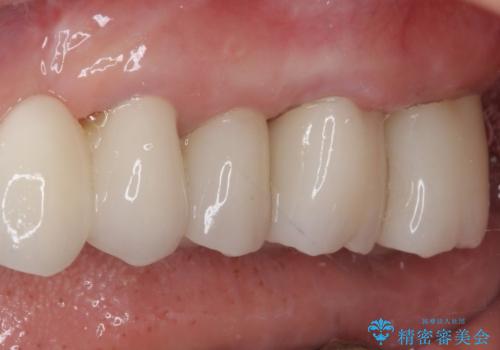

仮歯に置き替え、歯周外科処置(APF、歯肉弁根尖側移動術)による歯周ポケット除去を行った後に、オールセラミッククラウンにて補綴することとしました。

歯周外科処置により歯周ポケットを除去することができ、クラウン装着後はブラッシング時の出血や歯肉の腫れが気にならなくなりました。